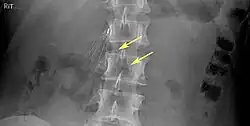

Of these IVC filter side effects, 328 involved device migration, 146 involved embolizations after detachment of device components, 70 involved perforation of the IVC, and 56 involved filter fracture. Much of the medical community believes that this large number of adverse events is related to the heart filter remaining in place for longer than necessary.

- Filter fracture

- 9% (12 of 132 patients) delayed filter penetration of the IVC greater than 3 mm

- Parts of filter broke off in 2% (5 of 230 patients)

- Caval filter migrated to heart or pulmonary artery (4 patients)

- Filter fracture: Broken struts migrate to retroperitoneum, requiring exploration.[21] Also struts can migrate to the heart and can cause pericardial effusion and tamponade.[22]